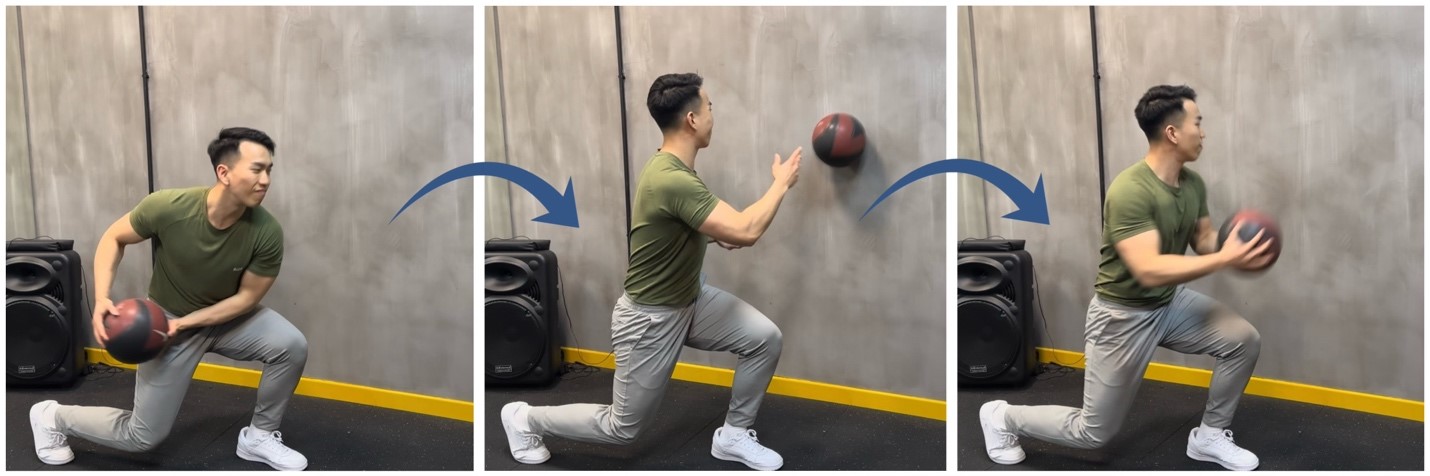

階段4 – 恢復功能 (受傷後12週以上)

- 當肩膀力量及活動範圍恢復後,逐步恢復運動或提舉重物等日常活動。

- 遵循治療師的建議,以確保安全地重返日常生活。

運動示例:特定運動的專項訓練 (Sports-Specific Conditioning Exercise)